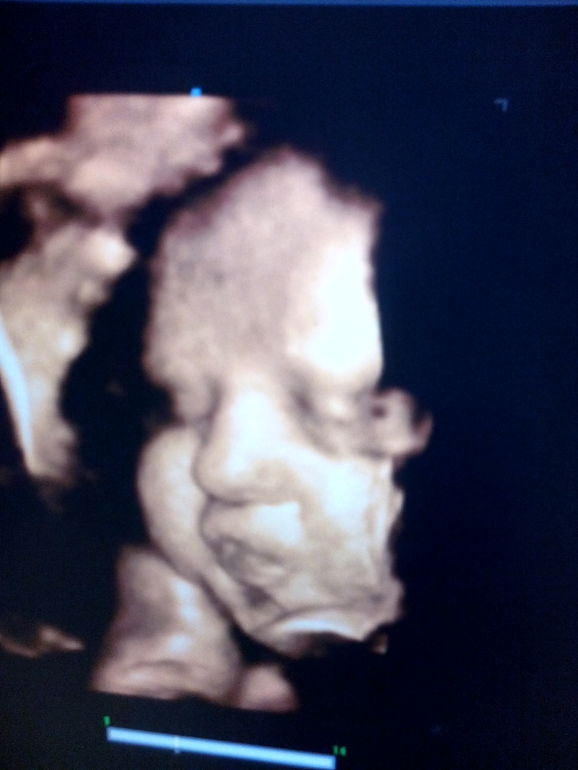

Домик моей принцессы на 35 недельке

А это первая фотография моей красоточки!